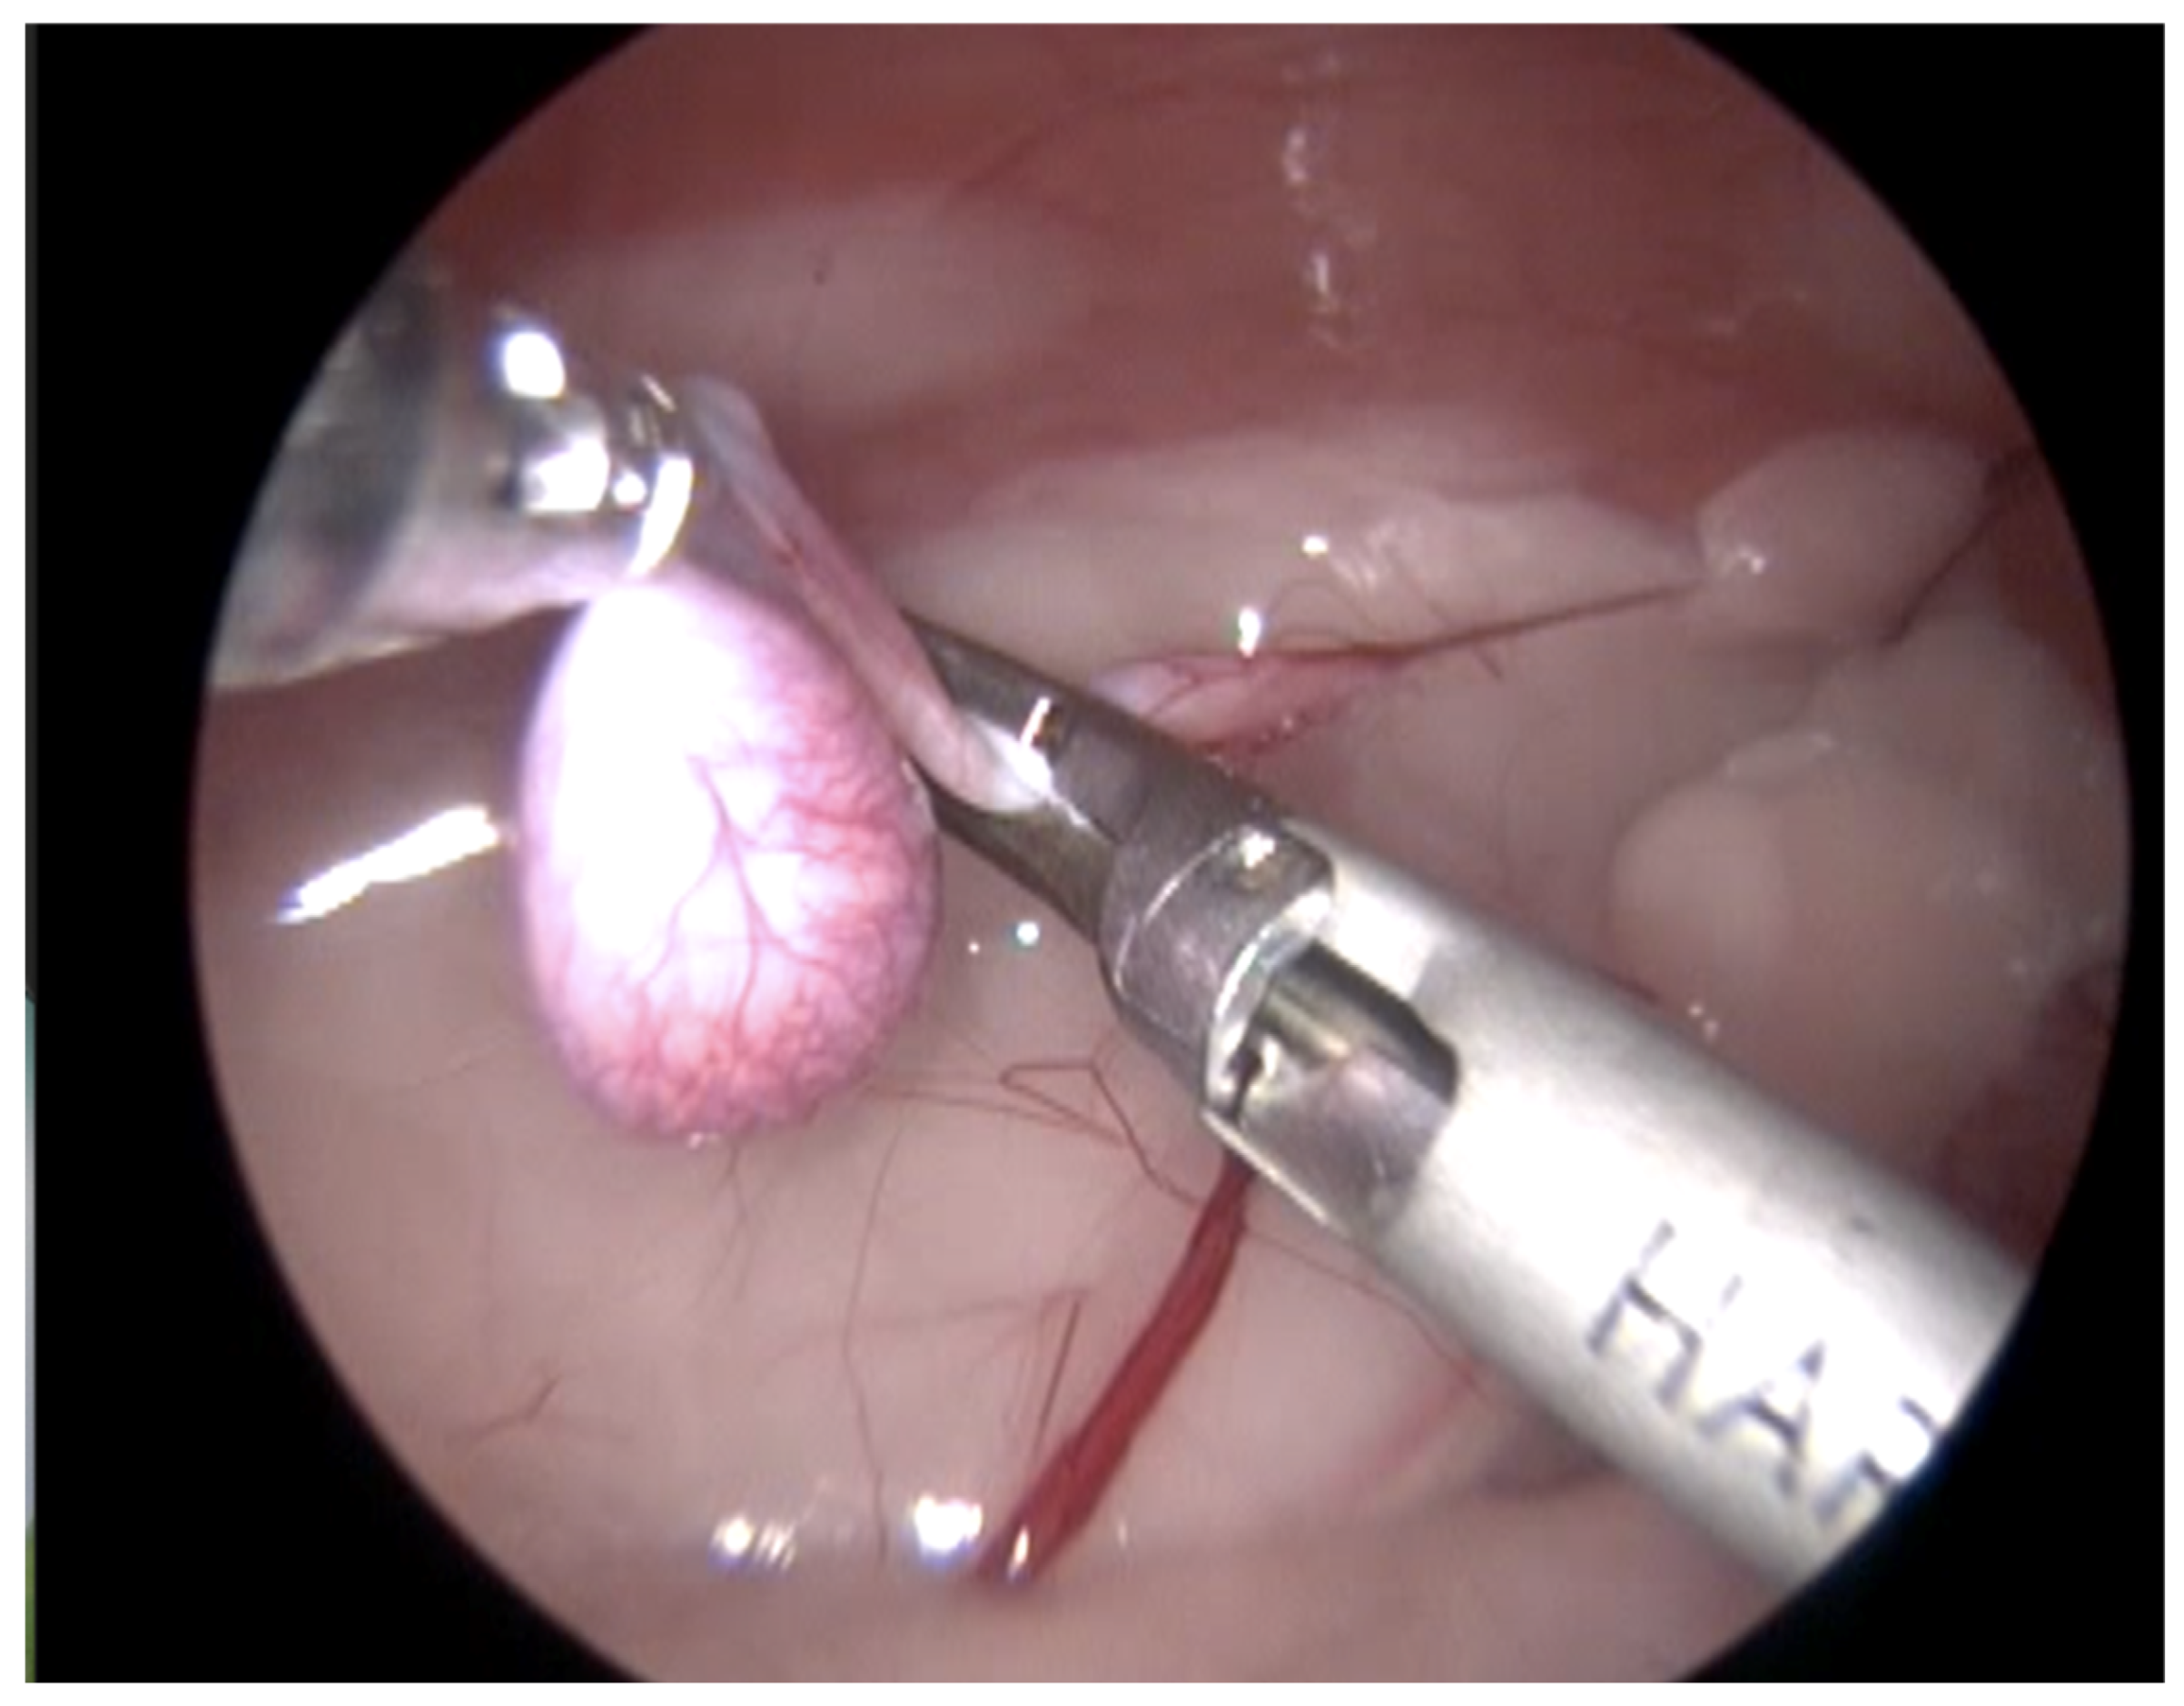

Figure 1.

Endoscopic image of the aspect of an intra-abdominal testis.

For the surgical procedure, in all cases, inhaled anesthesia was used, and anesthesia monitoring was performed by qualified personnel. In all cases, the main trocar was placed just caudal to the umbilicus using a Hasson technique in 10 cats, modified-Hansson in six cats, and the Veress needle technique in three cats. A small skin incision (<10 mm) was made at this site, and subcutaneous tissues were dissected to visualize the external rectus abdominis sheath; a small stab incision was made into the peritoneal cavity. In 16 cats, a 5 mm trocar was inserted through the incision, and a 6 mm trocar into the remaining 3 cats. The capnoperitoneum was achieved at a rate of 1–2 L/min to an intrabdominal pressure of 7–9 mmHg. A rigid 5 mm telescope with 0° or 30° angle vision was inserted through the trocar, and the abdomen was explored systematically. When an abdominally retained testes was detected, a second access port with a 5 or 6 mm trocar was inserted in a caudal position and slightly lateral to the retained testis, and particularly in the case of the three bilaterally cryptorchid cats, the second trocar was inserted in the center of the caudal abdomen. The second trocar placement was performed with the use of direct visualization through the laparoscope, and transillumination of the abdominal wall was used to avoid blood vessels. To be able to work with two trocars, external suture was used to suspend the testis. The size of the needle was dependent on the size of the animal but had a curvature and sufficient length to allow comfortable entry and exit through the abdominal wall. In the current clinical cases, a 3/8 circle reverse cutting needle ranging from 24 to 30 mm length was commonly used. With transillumination, the most appropriate place to insert the needle was located, avoiding vascularized areas. First, the needle was passed through the abdominal wall, under direct endoscopic visualization and then passed through the testis carefully avoiding vascular structures, and ultimately pulling the needle out through the abdominal wall again. The suture was secured externally with the help of a hemostat, thus fixing the testis to the abdominal wall. In three cases, a percutaneous grasping technique was performed using an open-loop grasper that allowed the testis to be fixed to the abdominal wall with a single puncture; and in three cases, a third port was implemented with two paramedian trocars. With these maneuvers, the detailed visualization of the vascular pedicle, the spermatic cord, and the gubernaculum was achieved (Figure 1 and Figure 2).